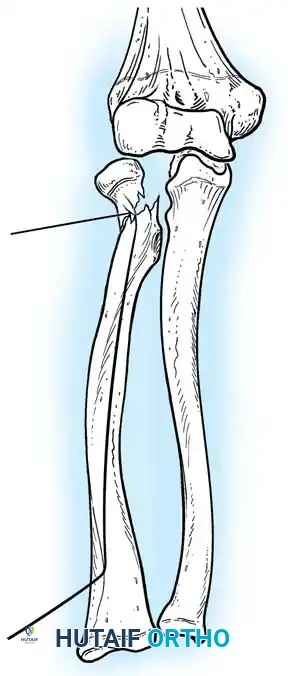

Fig. 33-36 Overcorrection with posterior convexity for anterior dislocation.